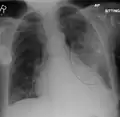

AP CXR showing right lower lobe pneumonia

AP CXR showing pneumonia of the lingula of the left lung